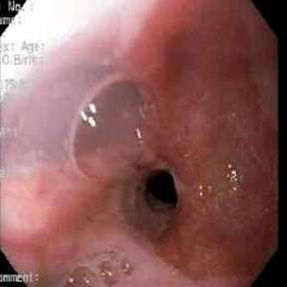

Se practicó una endoscopia de vías digestivas altas, en la cual se encontró una estenosis esofágica importante, secundaria a fibrosis y esofagitis péptica, que se pudo dilatar con un balón neumático de 2 cm (figura 2). El estudio de histopatología fue negativo para neoplasia maligna.

En un nuevo estudio endoscópico, se evidenció una estenosis de 10 mm de diámetro (figura 4). Se consideró que debía practicarse una herniorrafía hiatal con cirugía antirreflujo parcial, mediante abordaje laparoscópico.